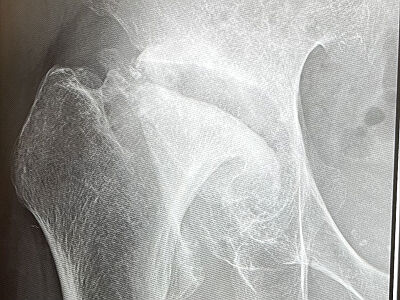

↑↑↑

潰れた骨頭と臼蓋との隙間が十分に空いているので、関節の動きに支障はありません。

10年前と比べると、臼蓋が少し削れているくらいですかね。